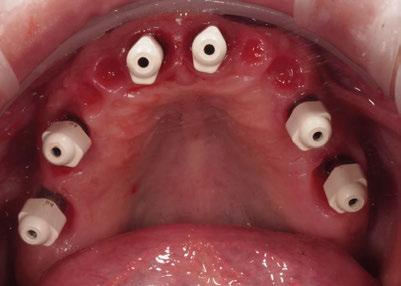

3. Fase quirúrgica final

A los 6 meses de cicatrización, se realizó un nuevo CBCT, obteniendo un nuevo archivo DICOM que alineamos con el STL del encerado. De esta manera, se planificó la posición de los implantes a 4 mm del margen de la restauración final y se diseñó y confeccionó la férula de cirugía guiada dentosoportada en 12-13 y 22-23, la cual imprimimos con la impresora 3D Formlabs®. El provisional

de carga inmediata lo diseñamos con el programa de diseño 3D Exocad® a partir del encerado y se imprimió también en clínica con la misma impresora 3D (Figuras 14-16).

La cirugía se realizó bajo sedación consciente y anestesia local (articaína 4% con epinefrina 40/0,01 mg/ml Ultracain®, 5 carpules en vestibular y palatino de la arcada superior). En primer lugar, se realizaron las exodoncias de los dientes remanentes 11, 21 y 24 y, a continuación, se adaptó la férula de cirugía guiada dentosoportada, insertando los implantes elegidos, en este caso en las posiciones 11 y 21 de Zimvie Tapered Screw-Vent Z3D de 3,7 por 13 mm, 14 Zimvie Tapered Screw-Vent Z3D de 3,7 por 13 mm y 16, 24 y 26 de Zimvie Tapered Screw-Vent Z3D de 4,7 por 13 mm, quedando todos ellos a un torque mayor a 30 Nm. Posteriormente, se realizaron el resto de exodoncias,

Seguidamente, se colocaron los pilares cónicos TSV-TM de Zimmer® y se atornillaron los pilares provisionales de titanio (Figuras 17-23).